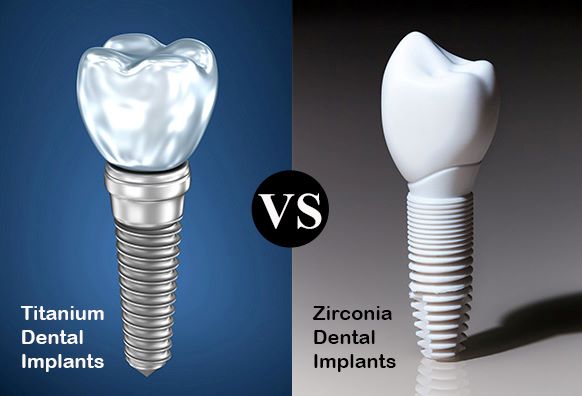

روکش ایمپلنت دندان: انواع، مزایا و انتخاب بهترین گزینه برای شما

روکش ایمپلنت دندان در ونک آخرین مرحله...

روکشهای ایمکس (E-Max) و زیرکونیا از جمله روکشهای سرامیکی باکیفیت برای دندانها هستند و هر یک ویژگیها...